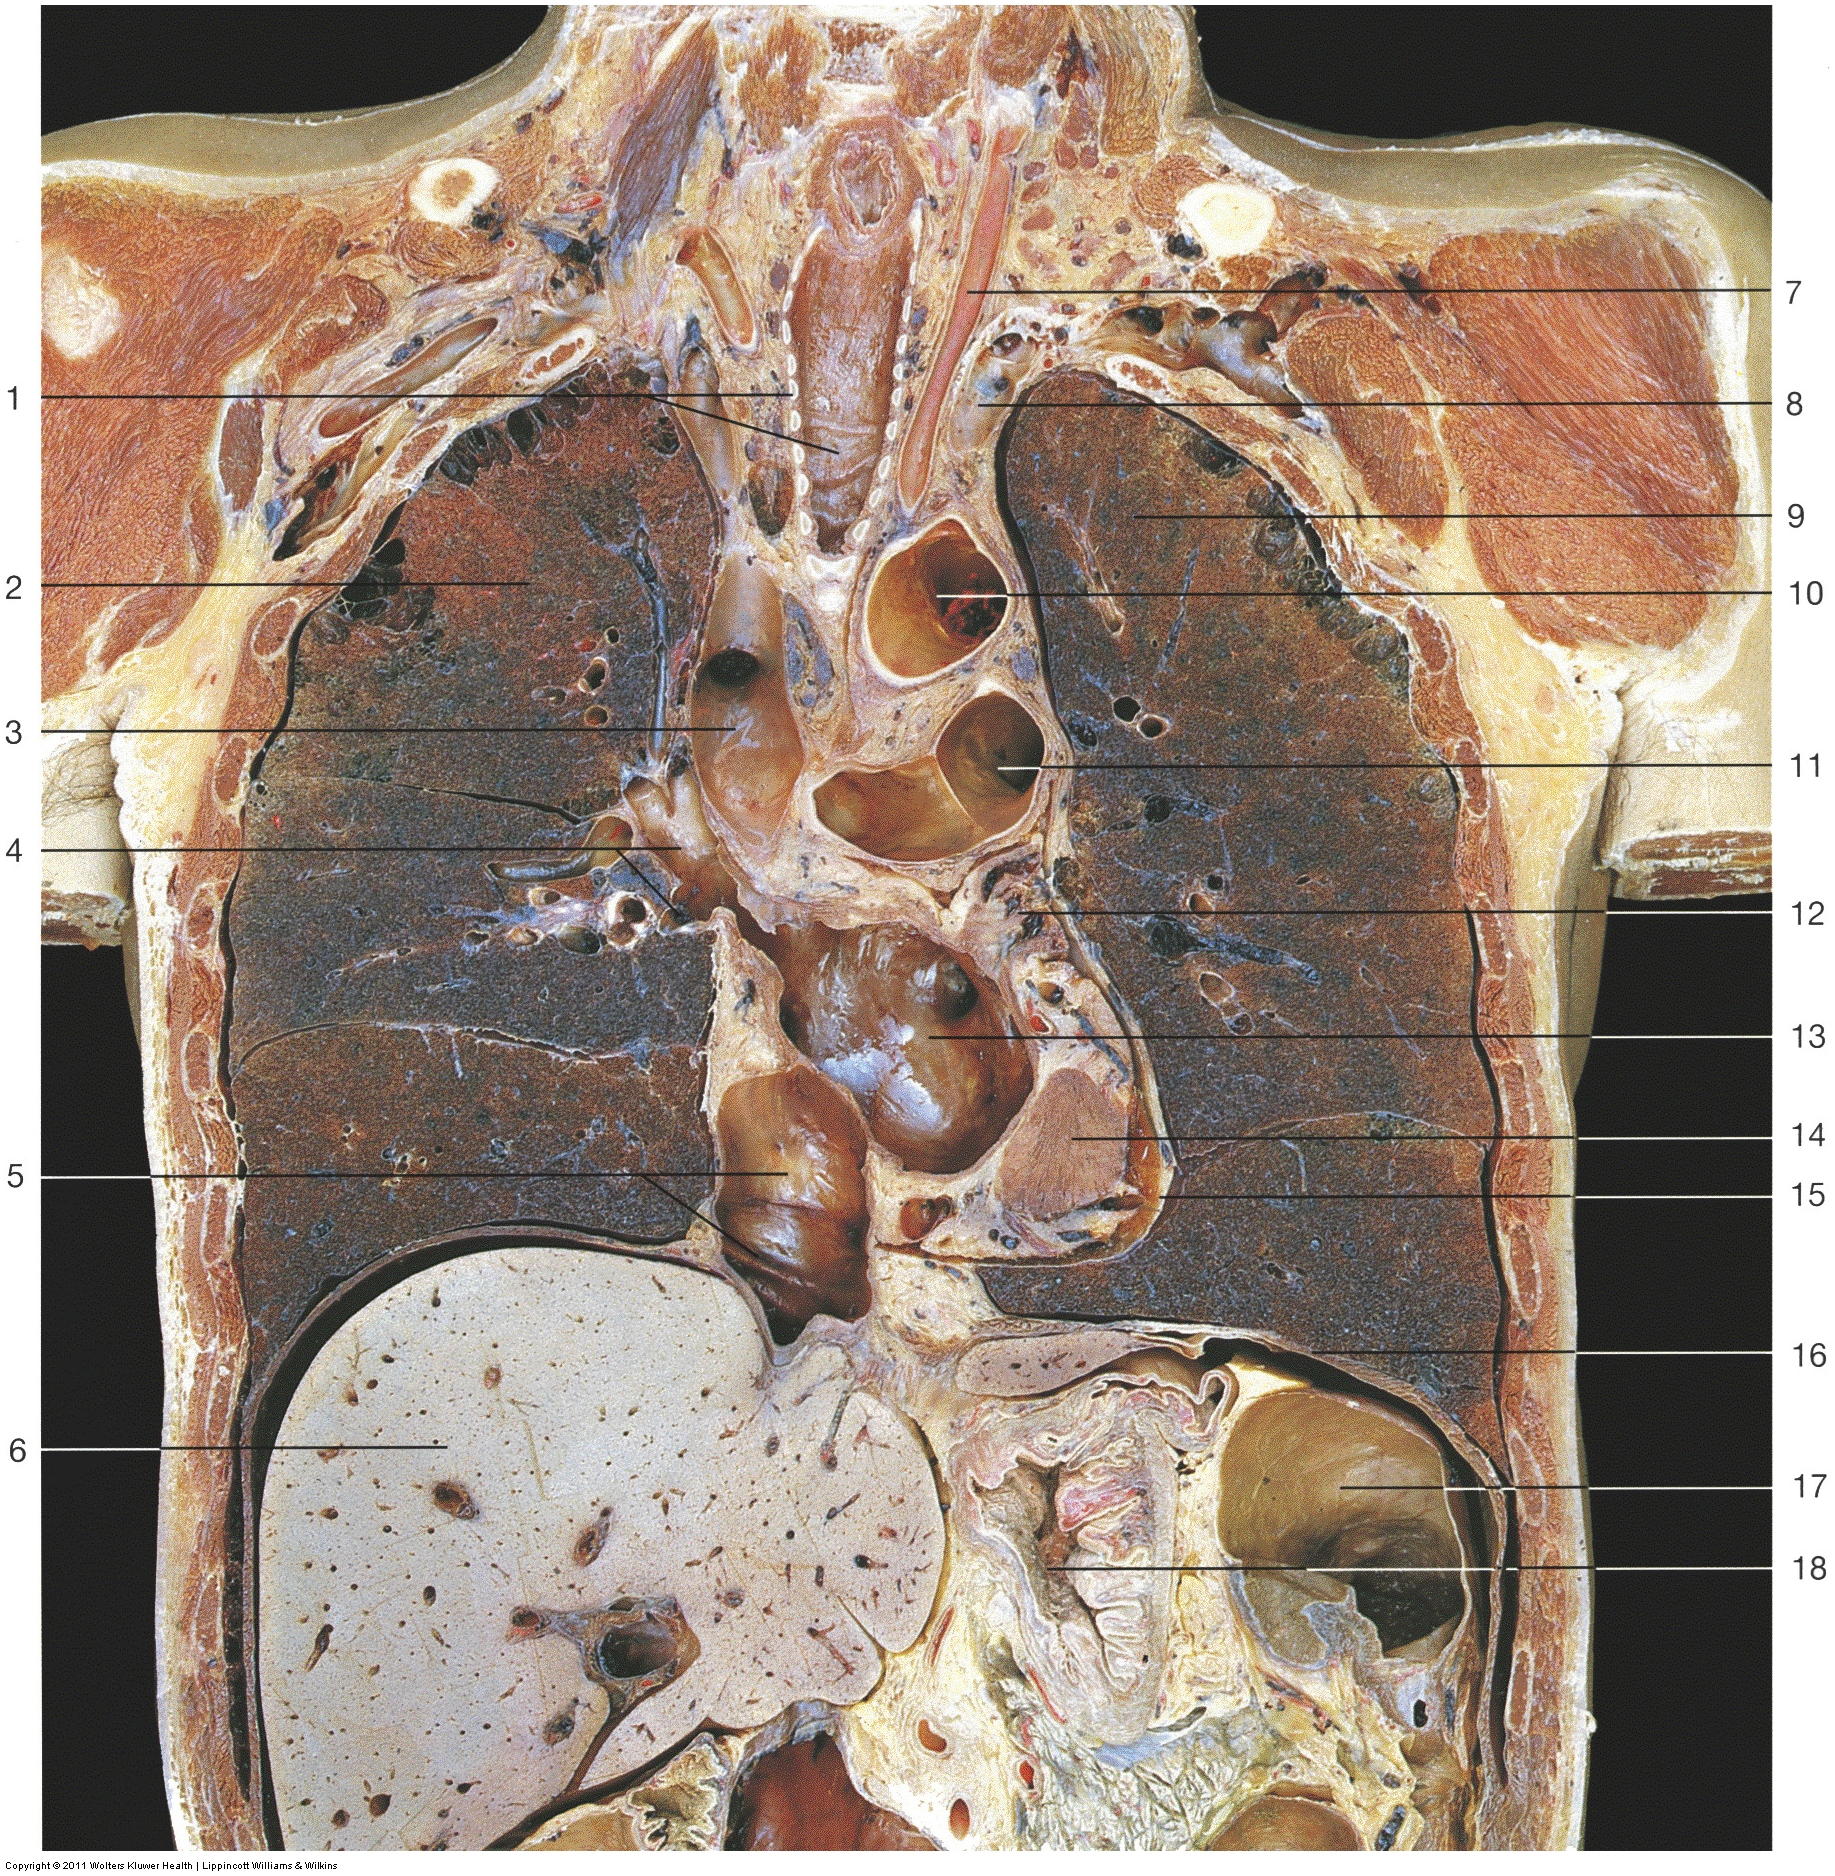

The diaphragm is the primary muscle used in the process of inspiration, or inhalation. It is a dome-shaped sheet of muscle (and connective tissue) that is inserted into the lower ribs. Lying at the base of the thorax (chest), it separates the abdominal cavity from the thoracic cavity. The diaphragm can clearly be seen separating the two cavities (label 16) in the coronal image below. It is a thin, skeletal muscle that can contract voluntarily.

See anterior view of the abdomen below: The oesophagus (label 7) and aorta (label 25) can be seen going through the diaphragm. The vena cava is seen on the right side as a hole in the diaphragm (label 10).